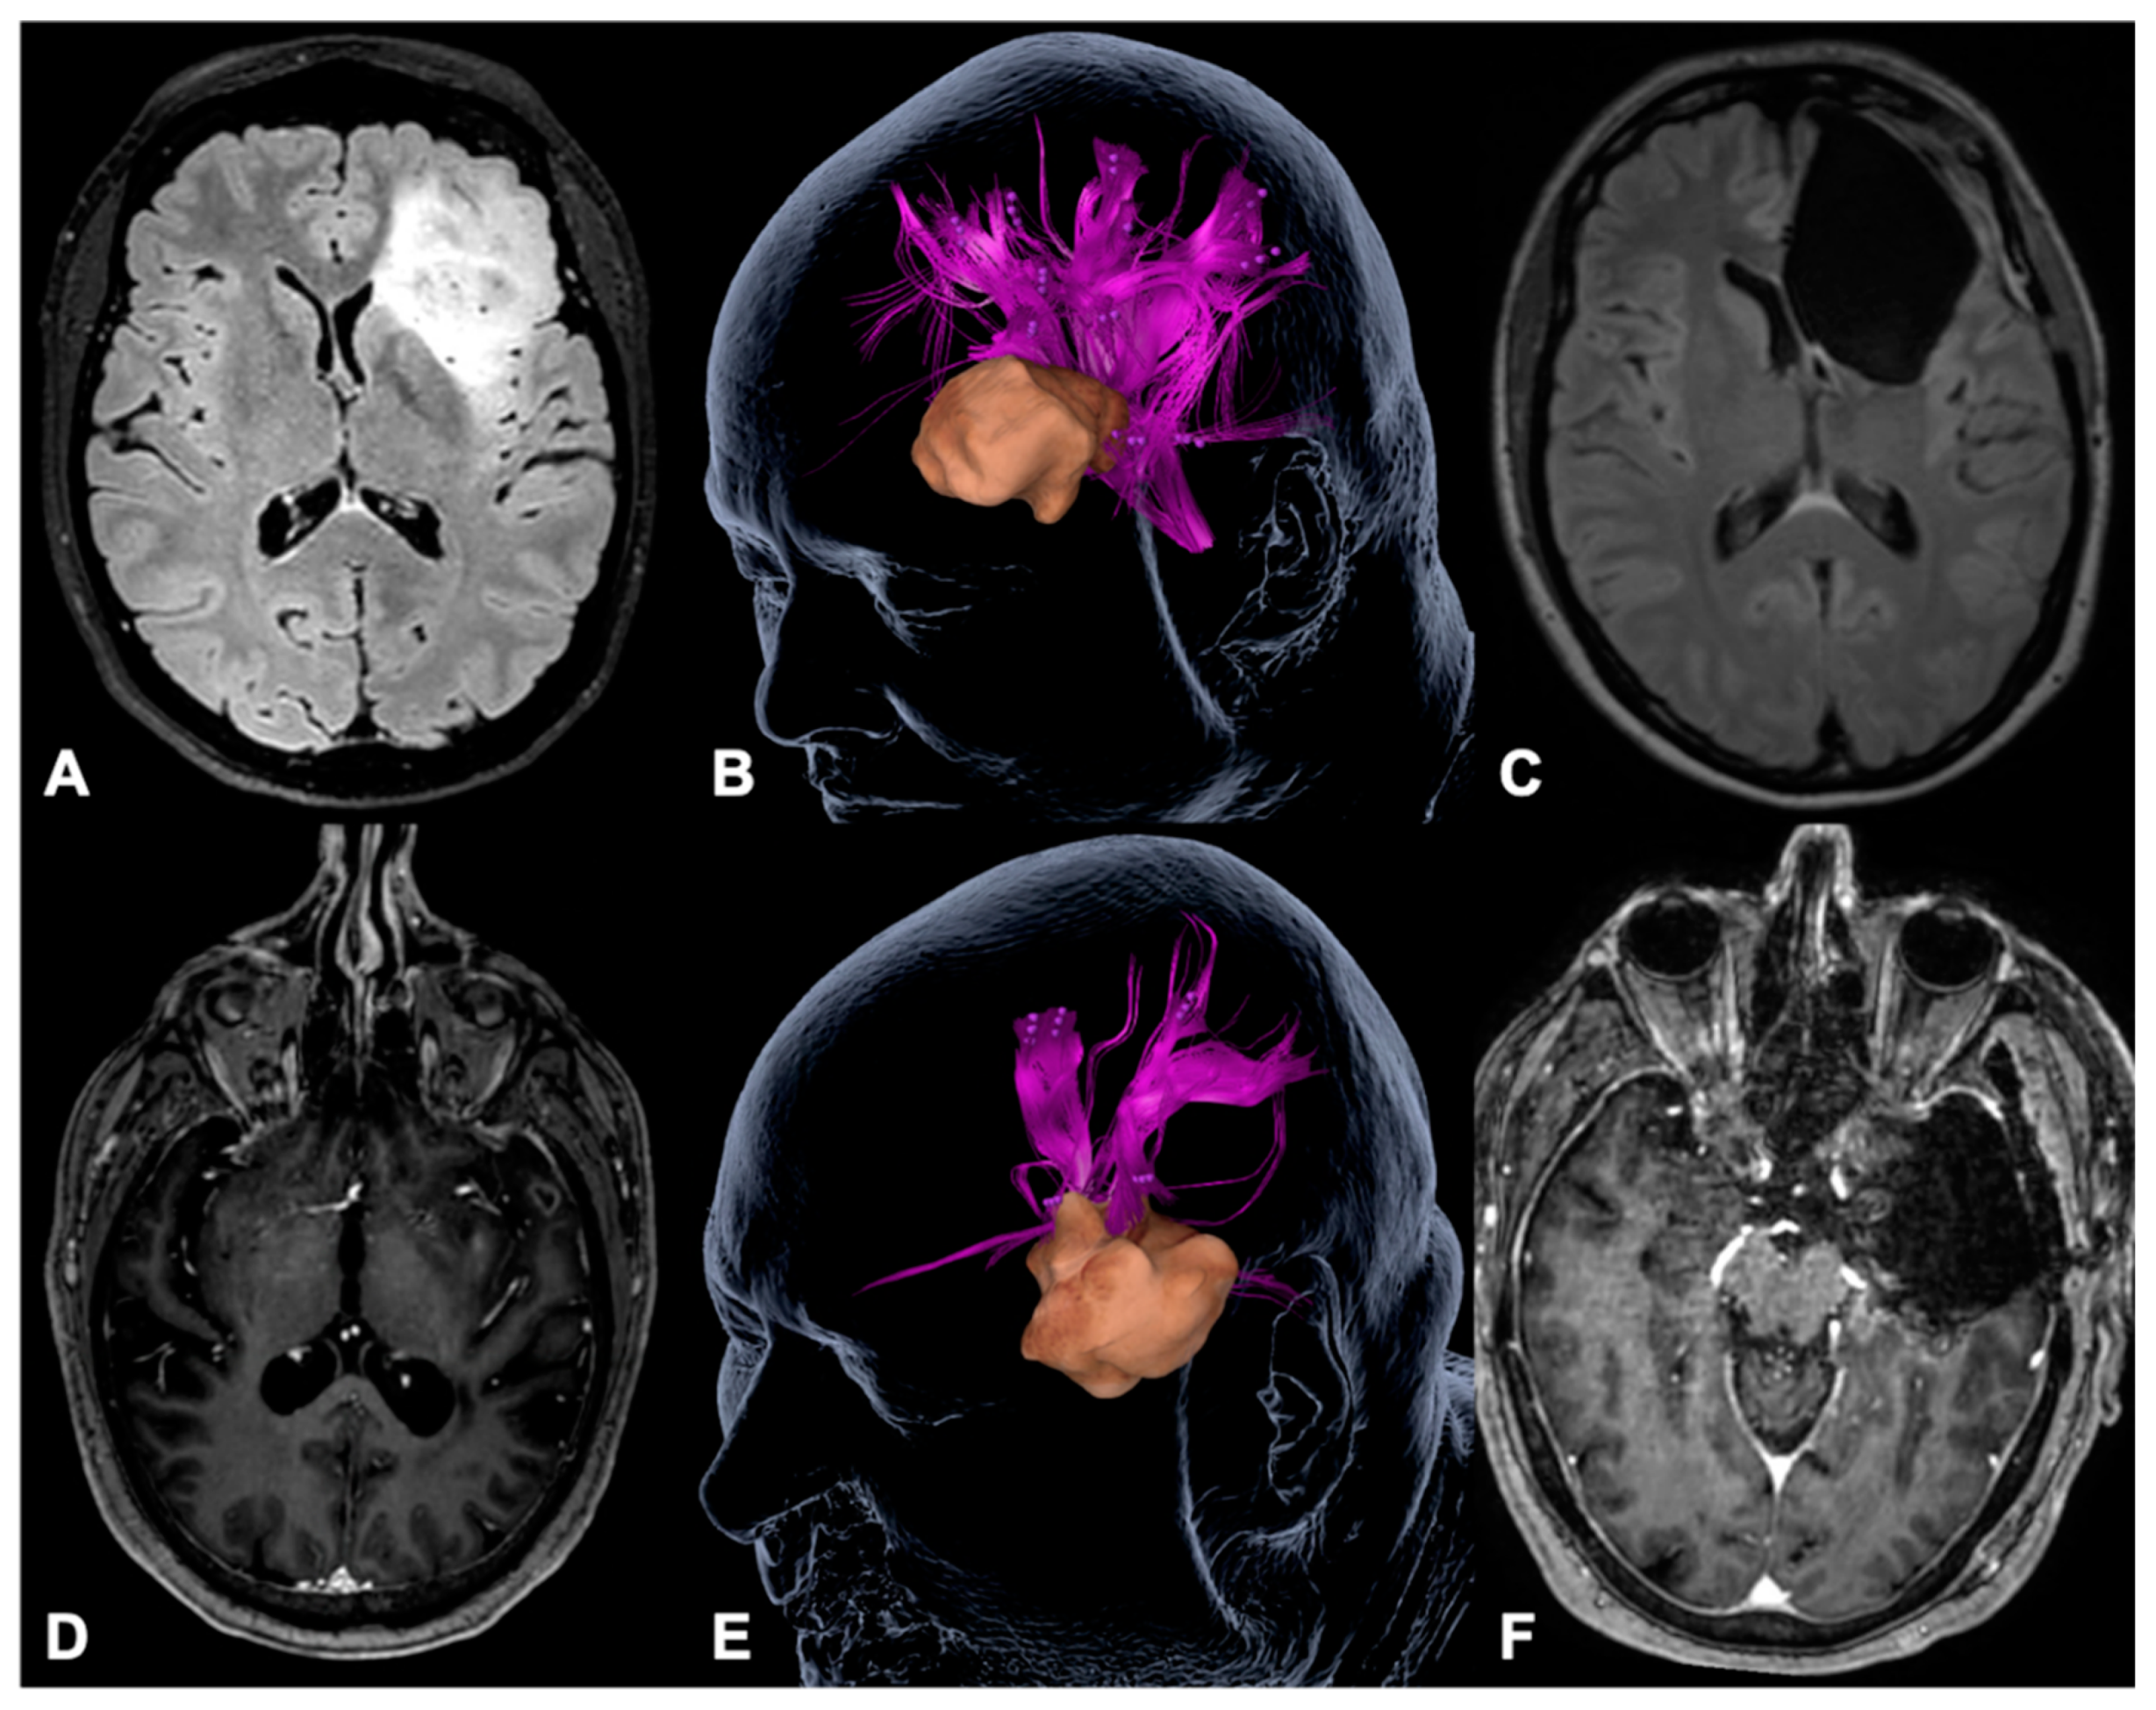

Figure 5.

Illustrative cases. The figure shows an illustrative case (A–C) of a patient suffering from a left fronto-insular diffuse astrocytoma WHO II (A), who underwent gross total tumor resection (C) based on DES language mapping during awake craniotomy after we found language-positive cortical sites in terms of nrTMS language mapping within the opercular part of the inferior frontal gyrus (pink sites, B). Clinically, the patient suffered from a slight transient fluent aphasia, grade 1B, postoperatively. The second patient (D–F) suffered from a left temporo-insular glioblastoma (D) and underwent gross total tumor resection (F) purely based on nrTMS language mapping data (E). The patient suffered from a slight transient non-fluent aphasia, grade 1A, postoperatively. Both patients did not show any permanent functional deficits.